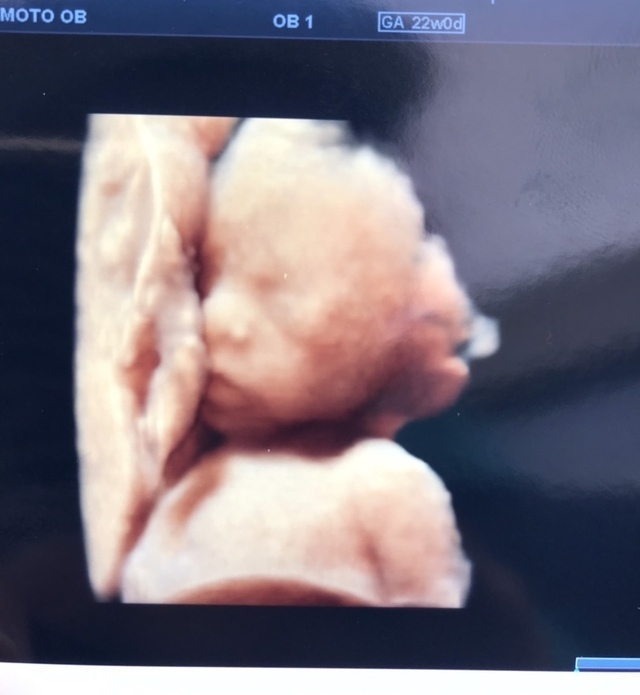

22週0日(22w0d・男の子)|3姉弟ママ さん(29歳)

エコー写真撮影時のエピソード:

3回目の妊娠。上の子同様、つわりも何もなくとっても健康妊婦。初めての3Dエコーでの写真。胎盤に気持ちよさそうに抱きついてる我が子をみて、愛しさがましました。無事に産まれてエコーのときのように抱っこで眠る我が子をみて幸せを感じてます。3Dエコーはリアルでちょっと怖い感じかなと思ってたのですが、自分の子供はやはり可愛く思えるものですね笑